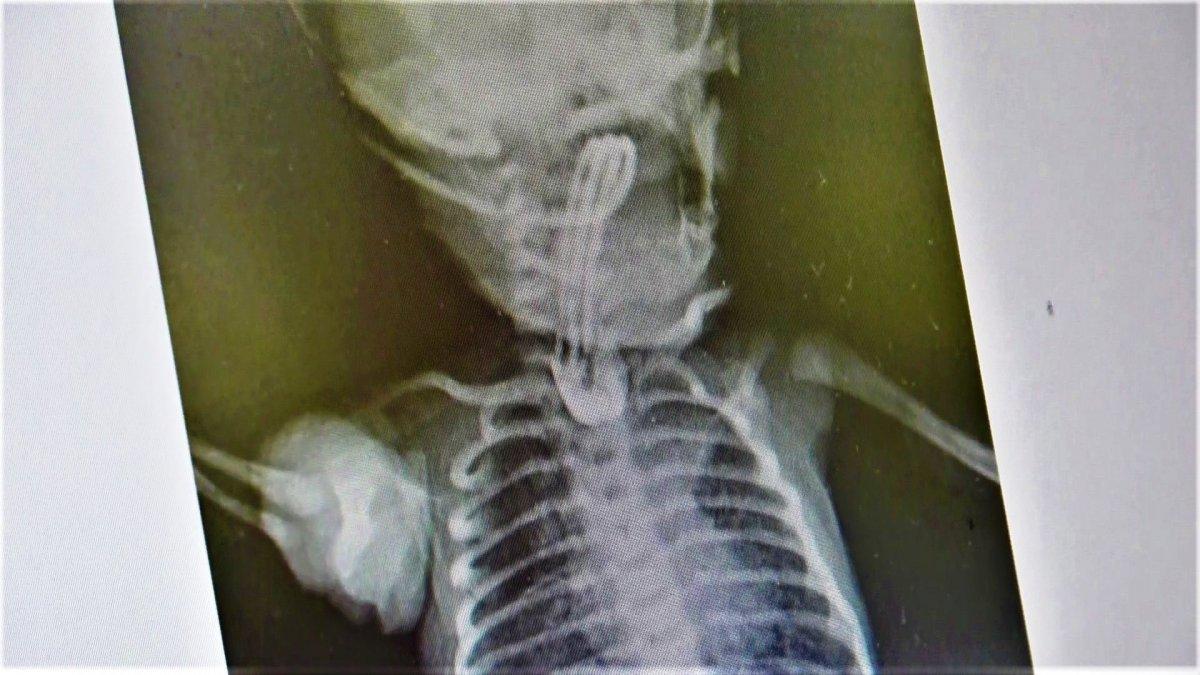

Aile, erken müdahale edilmediği takdirde çocuklarının öleceği gerçeği ile karşı karşıya kaldı. Kaya ailesinin başvurduğu özel hastanede, Çocuk Cerrahisi Uzm. Opr. Dr. Ayşe Bahar Edirne ve keibi tarafından bebeğin 3 santimetre olan yemek borusu ameliyatla 15 santimetreye çıkarıldı.

“Bebeğimiz doğduğunda yapılan ön tetkiklerde yemek borusunun olmadığı anlaşıldı. 2-3 günlük olduktan sonra ameliyatını gerçekleştirdik. 15 gün sonrasında da ağızdan beslemeye başladık. Yemek borusunun oluştuğunu çekilen filmlerde tetkik ettik. Sonrasında da ailesinin yanına verdik. Kontrolleri yapıldığında ise hiçbir problemi olmadığı görüldü. Eğer bu hastalık tespit edildiğinde zamanında tedavi edilmezse yemek borusu olmadığı için bebeğin beslenme şansı olmuyor. Ondan sonra da maalesef yaşama şansı olmuyor. Bu hastalık acil tedavi edilmesi gereken bir sorun.

Öncelikle ultrason ve ön tetkikler yapılıyor. Bütün hazırlıklar yapıldıktan sonra özellikle yeni doğan yoğun bakımın olduğu bir donanımlı bir hastanede bakımının yapılması gerekiyor. Ameliyat da başarılı geçtiği takdirde bu şekilde doğan bebekler hayata tutunuyorlar. Ameliyat yapılmazsa yaşama şansı olmayan bir hastalıktır. Binde bir ihtimalle karşımıza çıkıyor.”